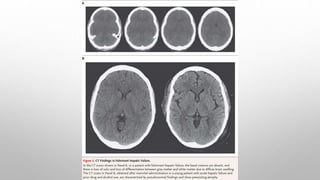

NEUROIMAGING –

• To exclude structural lesions.

Such as subdural hematomas or other evidence of cerebral trauma, or complications of alcohol abuse or thiamine

deficiency, or both, such as midline cerebellar atrophy, third ventricle dilatation, mamillary body atrophy, or high-

signal-strength lesions in the periventricular area on T2 FLAIR images.

• MRI T1 -abnormally high signals arising in the pallidum, T1 signal abnormality in the limbic and extrapyramidal

systems, and generally throughout the white matter. A generalized shortening of the T2 signal also occurs. ( An

increase in the cerebral manganese content).

• The abnormalities become more prominent with time and regress after successful liver transplantation.

• The unexpected finding of high T1signals in the pallidum should suggest the possibility of liver disease.